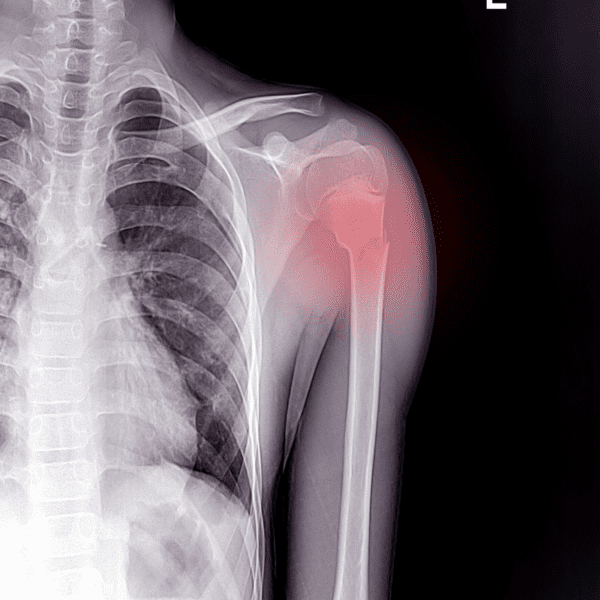

Een gebroken rib, ook wel een ribfractuur genoemd, kan ontstaan wanneer er veel kracht wordt uitgeoefend of gedrukt wordt tegen de borstkas. Dit kan gebeuren tijdens een auto-ongeluk, bedrijfsongeval of wanneer u van uw fiets valt. Voor het claimen van een schadevergoeding bij letselschade door een ribfractuur is het noodzakelijk dat er een verantwoordelijke partij is. Onze letselschade juristen helpen u graag met het claimen van uw schadevergoeding.

Letselschade bij gebroken ribben